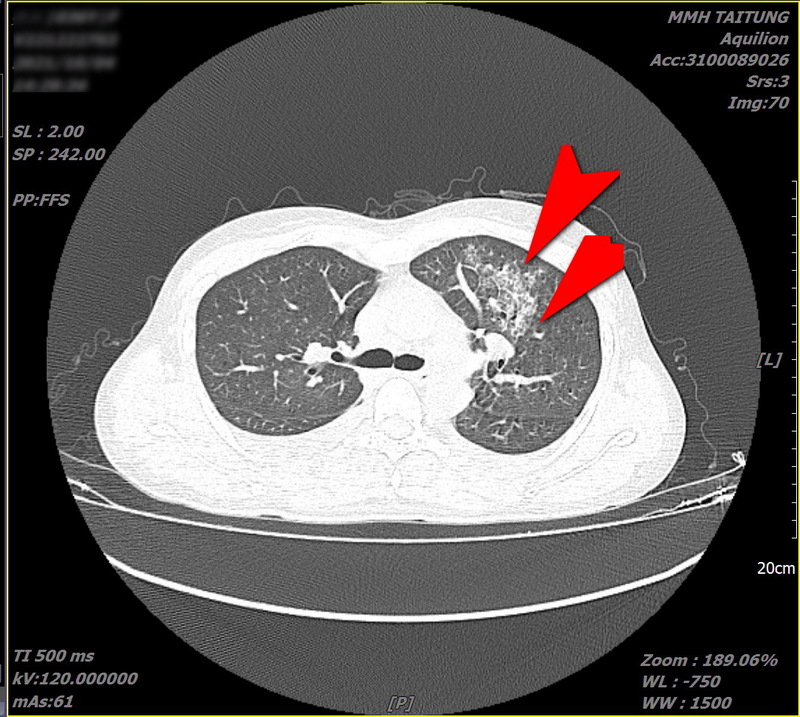

每年三、四月起,恙蟲病例數開始增加,鄭順賢醫師指出,日前收治一位女性病患,因高燒不退、呼吸急喘,先在北部就醫住院治療後要求出院,再到花蓮慈院急診。經過詳細檢查後發現她的右邊腰部有「焦痂傷口」,且肝功能指數異常,雙側鼠蹊部亦見淋巴結腫大,胸部電腦斷層檢查更發現左邊肺部有非典型發炎現象。

▲花蓮慈院日前收治一位女性恙蟲病病患,經過詳細檢查後發現她的右邊腰部有「焦痂傷口」,且肝功能指數異常,雙側鼠蹊部亦見淋巴結腫大,胸部電腦斷層檢查更發現左邊肺部有非典型發炎現象(如圖雙箭頭所指處)(鄭順賢醫師提供)